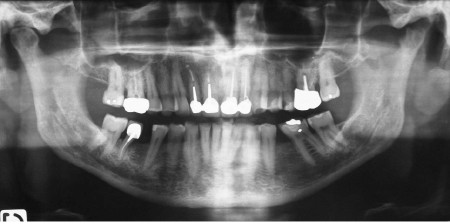

ATM : atteinte dégénérative de l’ATM gauche éventuellement en évolution.

Dents : soins dentaires à réaliser sur 16, 26, 37.

Amputation mésiale de 46 ?, légères érosions.

Arthrite dégénérative de l’ATM gauche s’inscrivant

probablement dans un trouble systémique.